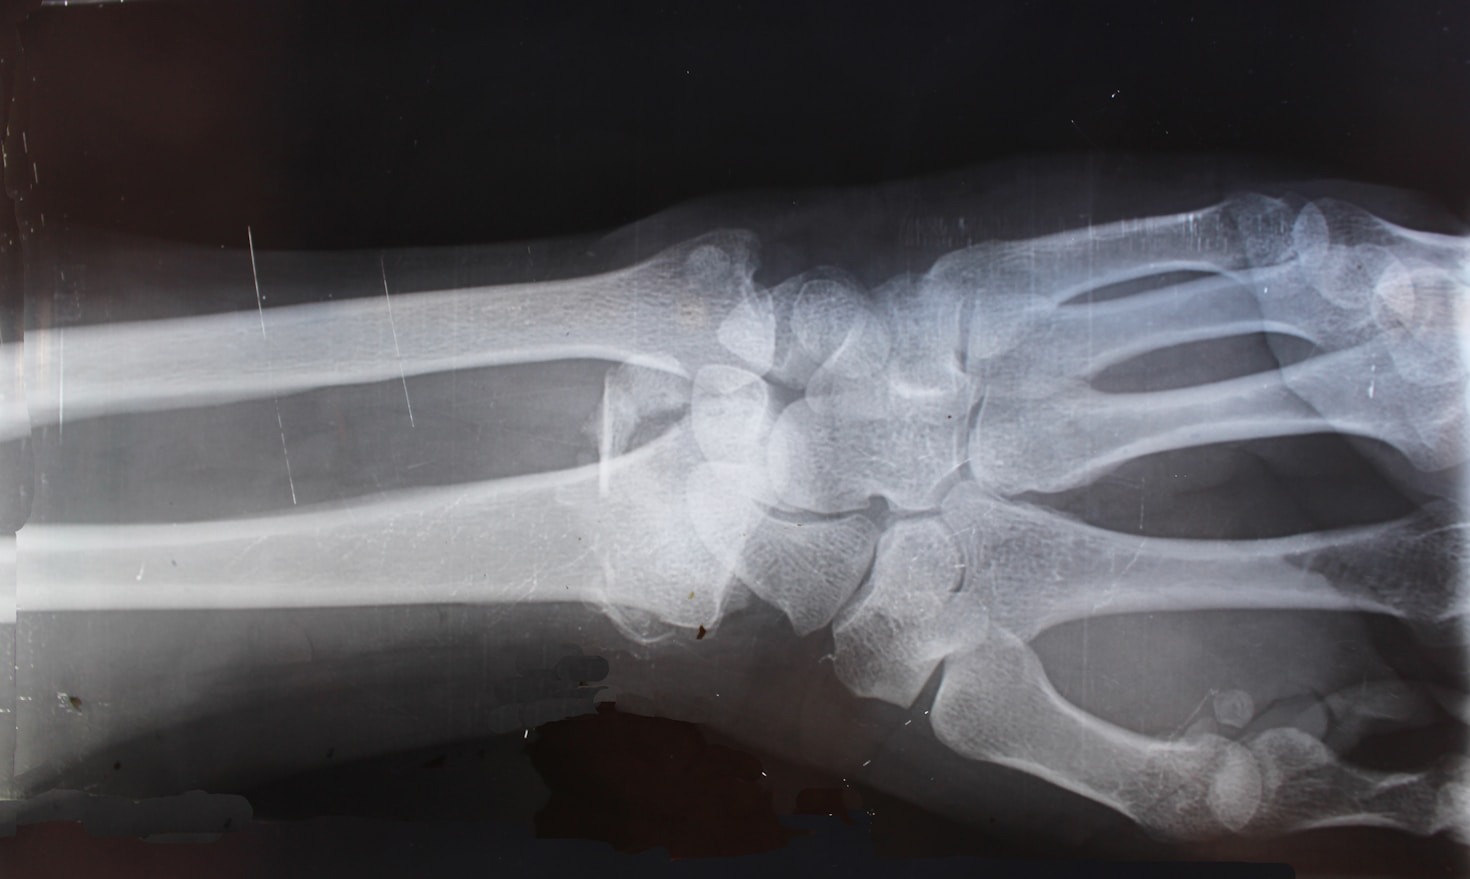

A área da radiologia está em constante evolução. Novas técnicas, novos equipamentos e o impacto da automação em todos os setores alicerçados pelo uso da inteligência artificial obriga os profissionais dessa área a estarem preparados para os desafios que se apresentam. Educação contínua é a palavra de ordem. Todo conhecimento atualizado é o que vai…